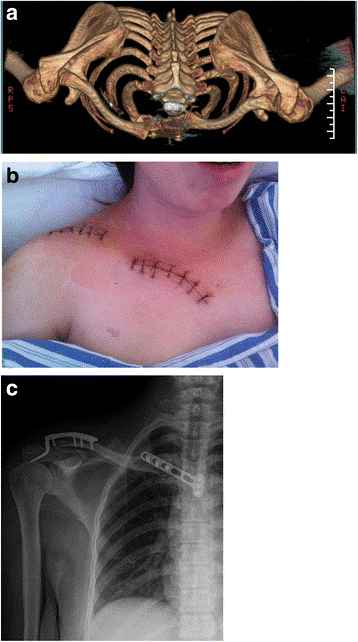

دراسات التصوير لخلع المفصل القصي الترقوي

الأشعة السينية

توفر الأشعة السينية صورًا لهياكل كثيفة ، مثل العظام. سيطلب طبيبك إجراء أشعة سينية على صدرك وكتفك من عدة زوايا مختلفة للمساعدة في تأكيد التشخيص واستبعاد أمراض الكتف الأساسية الأخرى.

من المعروف أن الاضطرابات في SCJ يصعب تصورها على الصور الشعاعية العادية الصور الشعاعية الروتينية للصدر لديها حساسية ضعيفة لالتقاط الاضطرابات .

التصوير المقطعي المحوسب (CT)

هذه الدراسة التصويرية أكثر تفصيلاً من الأشعة السينية العادية.

قد يطلب طبيبك إجراء فحص بالأشعة المقطعية لتقييم إصابتك بشكل أفضل وللمساعدة في التمييز بين الالتواء والخلع أو الكسر.